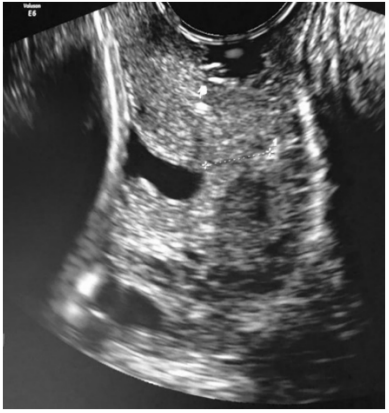

Uma primigesta com dezesseis semanas procurou o pronto-atendimento devido à sensação de peso em baixo ventre e cólica abdominal. Nega perda de líquido ou sangramento. Ao exame: altura uterina – 17 cm; ausência de contrações uterinas; BCF – 144 bpm; especular – colo epitelizado e ausência de sangramento ou leucorreia em fundo de saco vaginal; e toque vaginal – colo amolecido, posterior, médio e entreaberto. Foi encaminhada ao ultrassom, por meio do qual se observou a imagem seguinte.

Enunciado 3510886-1

Com base nesse caso hipotético, assinale a alternativa correta.